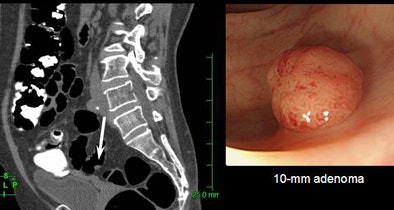

| Minimal-prep VC detected a 10-mm adenoma in the sigmoid colon (left); fecal tagging can be seen in the bright regions of the colonic lumen; colonoscopic confirmation is at right. All images courtesy of Janne Näppi, Ph.D., and Koichi Nagata, Ph.D. |